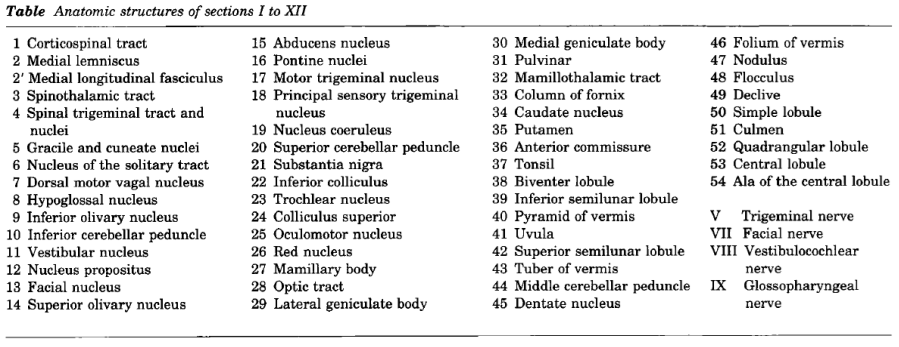

Cerebral vascular territories

Brainstem